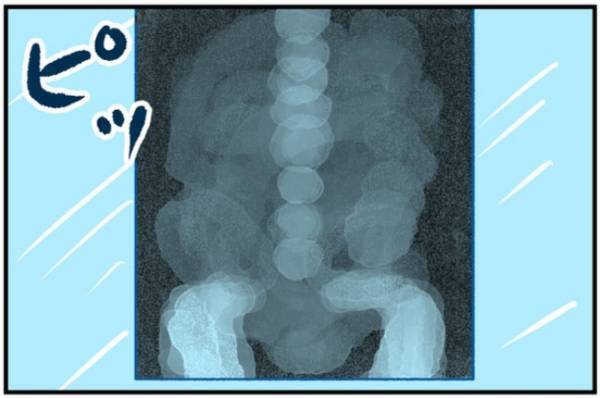

そして、最後にレントゲンでおなかの中を診てもらうことに。

大きな病気だったらどうしようとあれだけ不安になっていたのに、腹痛の原因はまさかの『便』でした。